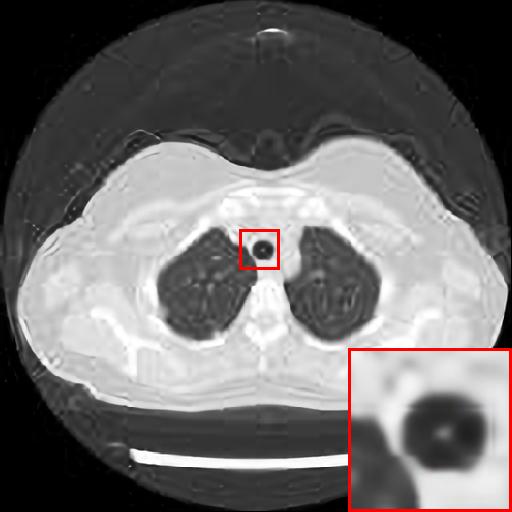

Figure 4: Reconstruction results of each algorithm for abdominal MRI images.

The PNSR/SSIM test results for the knee MRI test images for all contrast methods are shown in Table 1. The PNSR/SSIM test results for the abdominal MRI images are shown in Table 2. It’s worth noting that all metrics were calculated on cropped photos in order to eliminate the impact of non-subject areas. The quantitative results show that for knee MRI images, our proposed TT\mathrm{T}-GAN model achieves the best performance on the PSNR/SSIM metrics. For abdominal MRI images, our model essentially achieves optimal performance, with individual image WDSR slightly outperforming our model. The experimental results cousin that our model is more suitable for medical image super-resolution reconstruction than the existing deep learning-based image super-segmentation models.

We likewise give the visualization comparison results for each comparison algorithm, as shown in Fig. 3 and Fig. 4. It can be seen that the reconstructed images based on bicubic interpolation and deep learning based EDSR and WDSR both show oversmoothing phenomenon and some loss of detail information of the images. In contrast, our T-GAN performs better for the reconstruction of detail information due to the texture Transformer structure.